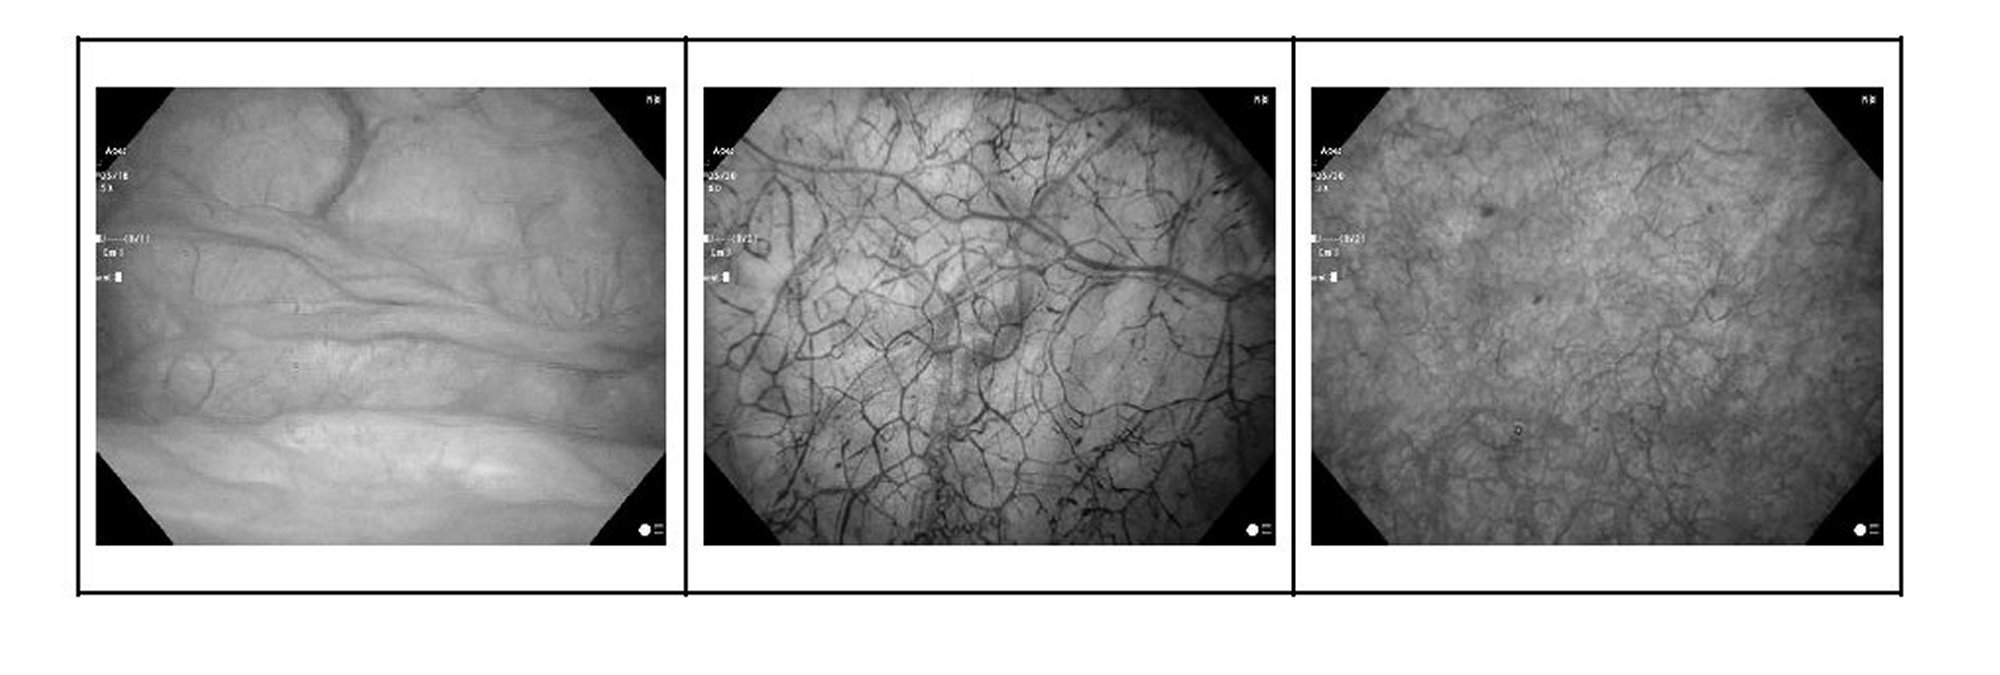

また、精度が高いアルゴリズムの獲得するために、多くのハンナ病変の態様を学習させる必要があるが、世界的には間質性膀胱炎患者の膀胱内視鏡画像の蓄積が非常に少ない。しかし、本発明者の上田朋宏は世界でも最も多くの間質性膀胱炎患者の膀胱内視鏡画像(および正常膀胱画像及びハンナ病変は存在しないが、正常膀胱ではない画像)を蓄積してきたことにより、多種多様のハンナ病変画像が蓄積されており、モデルの作成に十分な種類及び質の画像を学習させることができる。さらに、本発明では狭帯域光観察(Narrow Band Imaging,NBI)と白色光観察(White Light Imaging,WLI)のいずれの画像も学習させており、いずれの画像にも利用可能なモデルとなる。狭帯域光観察では、狭帯域化された青(390~445nmの波長)と緑(530~550nmの波長)の2つの波長の光が照射され、微細血管像のコントラストが増強されて出力される。青い光は粘膜表面の新生血管の有無を、緑色の光は粘膜深部の血管の有無を示す。白色光観察は、内視鏡の先端から青、緑、赤の3原色で合成される照明光を使用して観察する。なお、実際の医師による診断では、狭帯域光観察の方が病変を視認しやすいが、途上国を含む世界的な利用率では未だ白色光観察の方が高いと想定される。白色光観察は、病変も背景も赤に見える為に診断を難しくしている一因でもあるが、本発明では白色光観察画像にも適用可能であることから、汎用性が高く間質性膀胱炎患者の発見にも国際的合意形成にも有用である。 In addition, in order to acquire a highly accurate algorithm, it is necessary to learn many aspects of Hanna's lesions, but there are very few accumulations of cystoscopic images of patients with interstitial cystitis worldwide. However, Tomohiro Ueda, the inventor of the present invention, has accumulated the largest number of cystoscopic images of patients with interstitial cystitis in the world (and images of normal bladders and images of normal bladders without Hanna's lesions). A wide variety of Hanna's lesion images have been accumulated, and it is possible to learn images of sufficient type and quality for creating a model. Furthermore, in the present invention, both narrow band imaging (NBI) and white light imaging (WLI) images are learned, and the model can be used for both images. In narrow-band light observation, two wavelengths of narrow-band blue (390-445 nm wavelength) and green (530-550 nm wavelength) light are irradiated, and the contrast of microvessel images is enhanced and output. . Blue light indicates the presence or absence of neovascularization on the mucosal surface, and green light indicates the presence or absence of blood vessels deep within the mucosa. White light observation is performed using illumination light composed of the three primary colors of blue, green, and red emitted from the tip of the endoscope. In actual diagnoses by doctors, it is easier to visually recognize lesions with narrow-band light observation, but it is assumed that white light observation is still more popular worldwide, including in developing countries. White light observation is one of the factors that make diagnosis difficult because both the lesion and the background appear red. It is useful both for the detection of pneumonia patients and for international consensus building.

画像例

*上記泡の画像例は、ハンナ病がないが正常膀胱ではない画像例。

*原画像はいずれもカラー画像

Image example

*The above bubble image is an example of a non-normal bladder without Hanna's disease.

*All original images are color images.